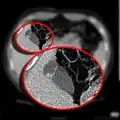

صورة مقطعية مُحوسبة تظهر القلنسوة الفريجية